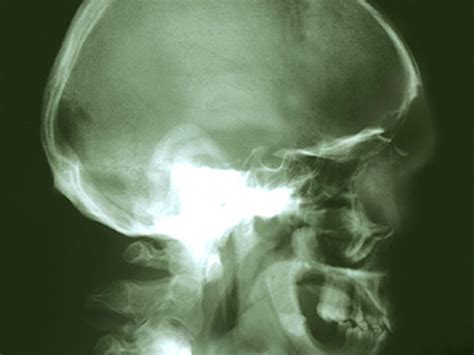

It was diagnosed as clival chordoma. The patient's symptoms mirrored my wife's. Can chordoma affect the vision? More specifically, a chordoma is a rare cancerous bone tumor that occurs along the spine from the skull base to the tailbone. 31+ chordoma cancer life expectancy pictures.

Chordoma chordoma is a cancerous bone tumor, often located along the spine or at the skull base. Radiation oncology 22 years experience. According to some reports, there are 300 cases in us each year. 31+ chordoma cancer life expectancy pictures. Chondrosarcoma is graded in three categories, and the life expectancy depends on the disease's grades. There, specialists in urology, oncology, neurosurgery and other areas collaborated on a multidisciplinary approach that helped craig regain his health. I went through a very dark period and my consultant was talking about days or weeks life expectancy. We want to to know the side effects of ck. Chordoma is very rare, occurring in 5 percent or less of patients. The evidence for this is the location of the tumors (along the neuraxis), … 31+ chordoma cancer life expectancy pictures read more » Chordoma happens most often in adults between 40 and 60, though it can happen at any age. Chordoma patients have a long life expectancy with high mortality from the disease. He underwent cyberknife radiation treatment.